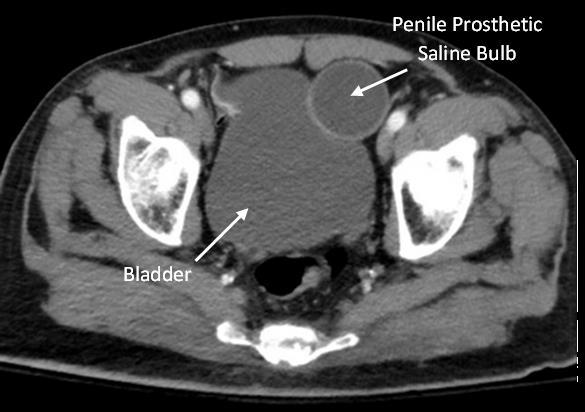

110 Implanted Penile Prosthetic Visualized During Focused Assessment with Sonography for Trauma

Examination: A Case Report

K Chambers, G Comp